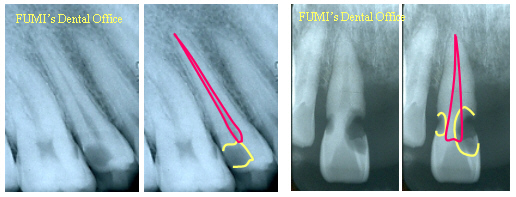

C2では歯の頭部分に黒い影が見えますが、神経の穴には達していません。虫歯の位置によって見え方は異なります。

C3では虫歯の黒い影が神経の穴とつながっています。歯髄炎では根の先端に異常はみられません。

根尖性歯周炎では根の先端に膿の袋を示す黒い影がみられます。

C4では根だけになっていることが確認できます。